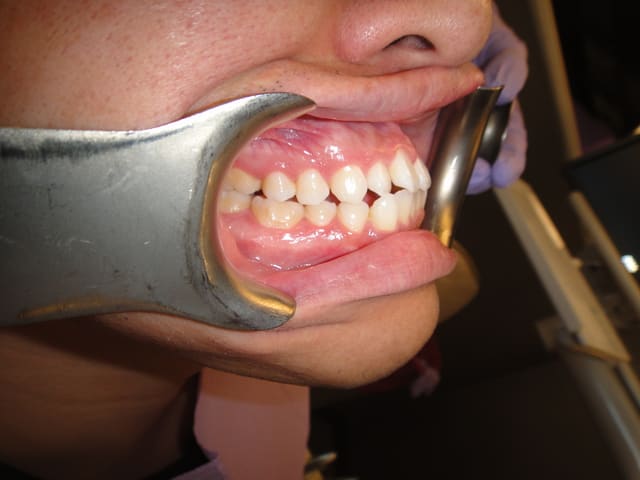

Patient asiatique, 25 ans, consulte car il veut corriger son crossbite bite antérieur localisé aux latérales et son crossbite secteur 2/3. Il aimerait également corriger son apparence générale, son profil notamment.

Classe III squelettique et dentaire.

Pas de shift à la fermeture.